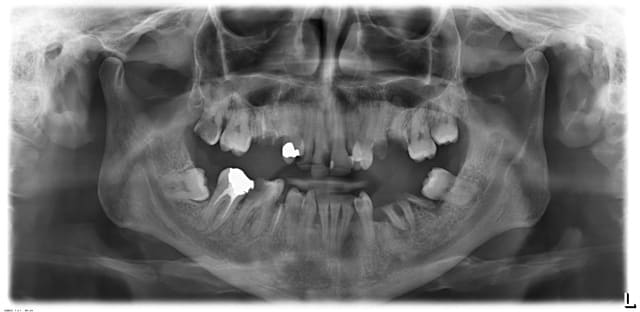

Jeune femme venue en urgence pour des douleurs en haut, en bas, à gauche et à droite.

Elle se brosse les dents au mieux une fois par jour et boit des jus de fruits/sodas toute la journée à la paille (manifestement positionnée en regard des 12 et 13: son sourire est merveilleux)

Elle vient pour que je gère ses douleurs sachant qu'elle est enceinte de 7 mois et demi mais n'a pas jugé bon de consulter plus tôt car les douleurs passaient toutes seules.

Pour l'instant j'ai ouvert la 27 qui semblait la plus douloureuse et lui ai demandé de revenir en soins sans sa gamine de 2 ans qui a chouiné tout le long du soin. Je suis un peu désabusée devant ce genre de cas. Que feriez-vous

-4 pulpites + absence d’hygiène .

-La patient qui ne vient que si épisode douloureux .

La motivation est donc proche de 0 .